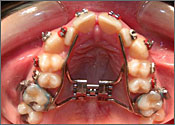

Palatal Expander